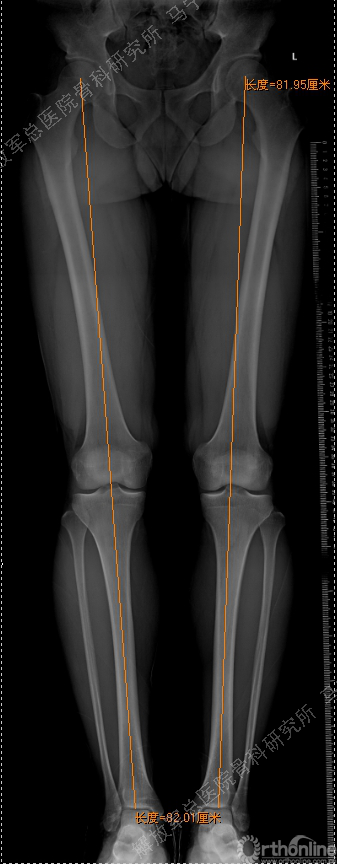

虽然是软骨损伤,但也需要X线评估关节结构,测量双下肢力线,髌骨轨迹,Q角等,排除结构因素引起的软骨损伤,若术前存在发育不良,脱位,半月板损伤,交叉韧带损伤,必须先进行矫形,最后再进行软骨修补,才能达到最佳效果和持久性。